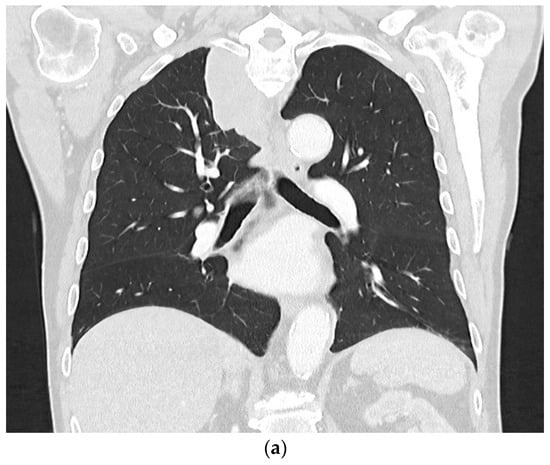

2. Primary Pulmonary Sarcomas

3. Pleural Mesothelioma